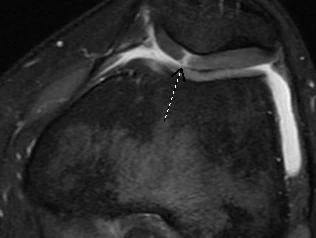

Your symptoms (pain, swelling, mechanical symptoms) may indicate to your physician if cartilage damage is to blame. X-rays and advanced imaging, including MRI, can show areas where cartilage has worn away.

An MRI from the same patient's knee. The arrow points to the area on the patella (kneecap) where healthy, intact cartilage is missing.

An MRI from the same patient's knee. The arrow points to the area on the patella (kneecap) where healthy, intact cartilage is missing.How Can I Protect My Joint Cartilage?